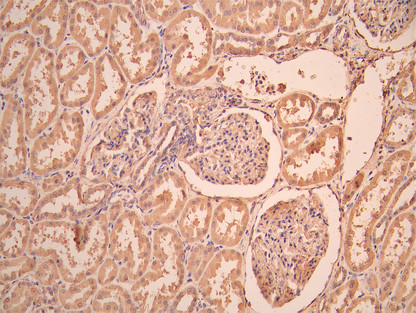

• IHC image of CSB-RA623101MA1HU diluted at 1:50 and staining in paraffin-embedded human kidney tissue performed on a Leica BondTM system. After dewaxing and hydration, antigen retrieval was mediated by high pressure in a citrate buffer (pH 6.0). Section was blocked with 10% normal goat serum 30min at RT. Then primary antibody (1% BSA) was incubated at 4°C overnight. The primary is detected by a Anti-Human lgG, Fcy Fragment Specific labeled by HRP and visualized using 0.05% DAB.